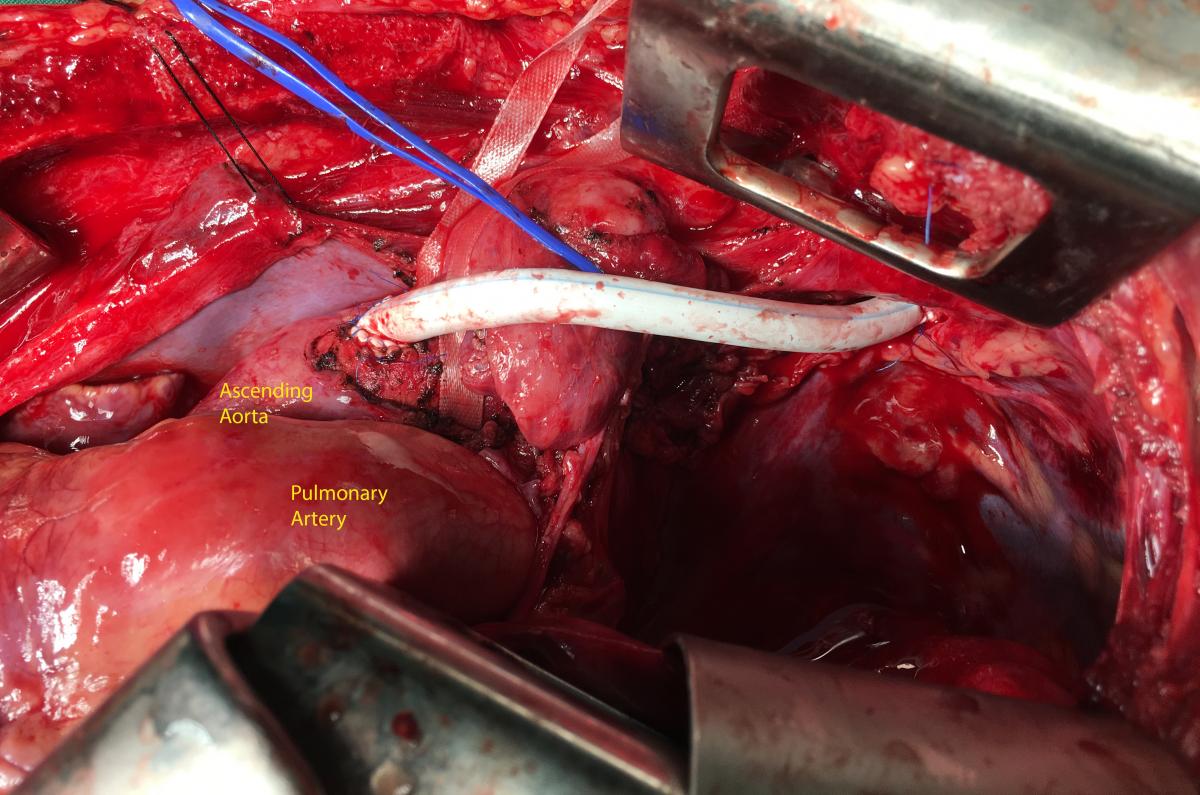

When the thorax was opened, the surgical team discovered the left pleural cavity flooded with blood and bleeding from the left ruptured subclavian artery, about 1 cm from its origin. There was no pericardial effusion. The bleeding artery was occluded quickly with two vascular clamps while the resuscitation continued with direct cardiac massage, vasoactive agents, solutions, and blood infusion (Figure 2). During the next 15 minutes, the heart returned a ventricular fibrillation and two direct electric shocks of 10 joules were applied, the sinusal rhythm then recovered and blood pressure was resumed. From that time until the end of operation, the hemodynamic parameters well-controlled in the acceptable range, with medium blood pressure around 60 mmHg. The patient’s two pupils were moderately dilated (about 4 mm) and almost slowly reactive to light.

The left subclavian artery was ruptured about 2 cm of length, but the arterial wall was contused longer than the ruptured portion—this extended from the origin of subclavian to the left vertebral artery. The origin of subclavian artery was sutured with pledgets on the aortic wall, and a bypass with Gore-Tex 6 mm diameter was realized between ascending aorta and subclavian artery (the postlesion segment). The proximal and distal anastomoses were made with a termino-lateral and a termino-terminal type, respectively. The flux of left vertebral artery was preserved (Figure 3).